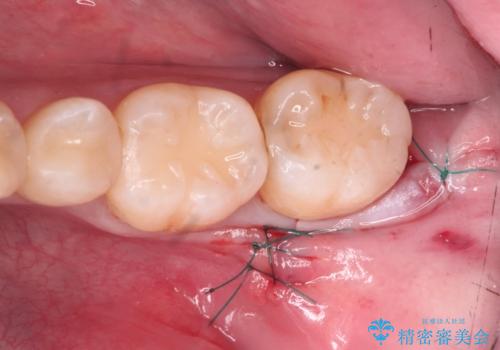

親知らず抜歯

- 親知らずを抜きたいとのことで来院。

パノラマ写真(二次元的な写真)だと、下歯槽神経が近いかどうかわからないので

CT(三次元)を撮り、神経が近くないことを確認して抜歯を行いました。

- 外科手術のため、術後に出血、痛みや腫れ、違和感を伴います

- 口腔内の状態によっては適応できないことがあります